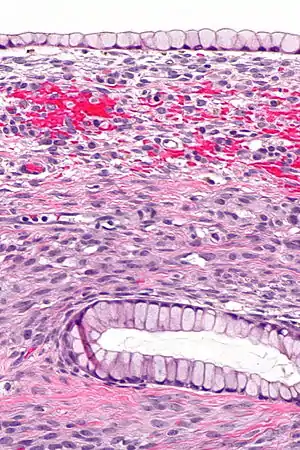

| Micrograph showing a mucinous cystadenoma of the ovary. H&E stain. | |

Microscopy